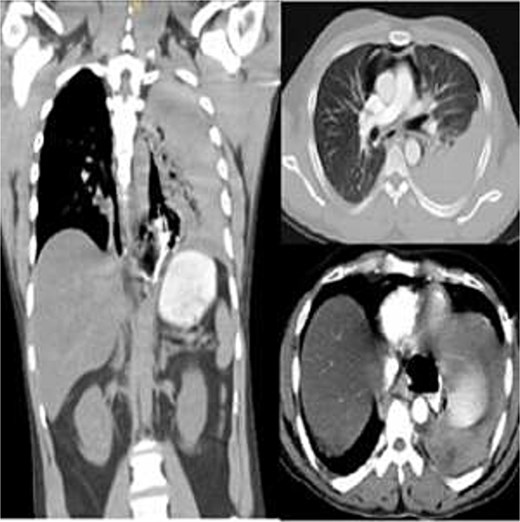

Due to high suspicion of esophageal perforation, a contrast-enhanced chest-abdomen CT (oral and IV contrast) revealed extensive pneumomediastinum, contrast extravasation from the lower third of esophagus, and hydropneumothorax (Fig. 1). Following evaluation, Boerhaave syndrome was confirmed. The patient was stabilized in ICU, and an urgent thoracic consultation obtained.

Contrast-enhanced chest CT showing distal esophageal perforation with pneumomediastinum and left hydropneumothorax.